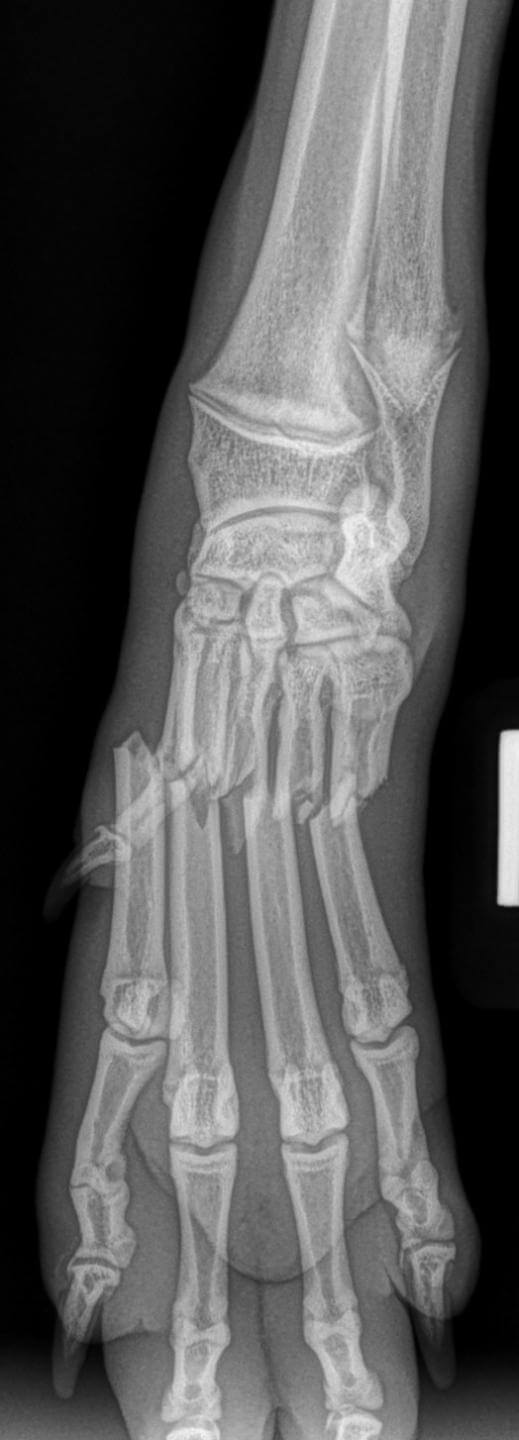

Thoracic Limb Fractures

Radius/Ulnar